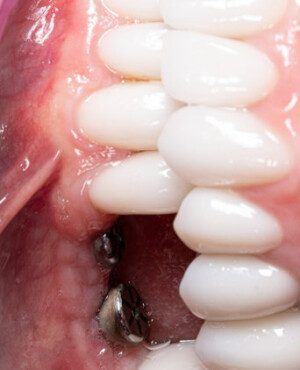

După extracția dentară, în intervalul de 6-12 luni, osul alveolar suferă un proces natural de remodelare, ceea ce conduce la scăderea volumului osos prin rezorbție. De aceea, inserția implantului dentar este ideală imediat după extracție sau, cel târziu, în primele 3-4 luni după aceasta.Scopul procedurilor de adiție osoasă este refacerea fundației osoase necesare pentru stabilizarea corectă a implantului dentar. Pentru ca un implant să reziste în timp la forțele masticatorii, este nevoie de o bază osoasă solidă și sănătoasă.

Aditia gingivală este o procedură chirurgicală ce corectează diverse probleme estetice și funcționale, cum ar fi recesiunea gingivală. În implantologia modernă, aditia de țesut moale este utilizată aproape în fiecare intervenție de inserție a implantului dentar pentru a asigura un aspect estetic natural și o bună integrare a implantului în cavitatea bucală.

Adiția osoasă are un rol crucial pentru poziționarea corectă și stabilă a implanturilor dentare. Clinica stomatologică Dr. Grossu din Chișinău promovează o abordare chirurgicală estetică și predictibilă, adaptată fiecărui caz în parte.